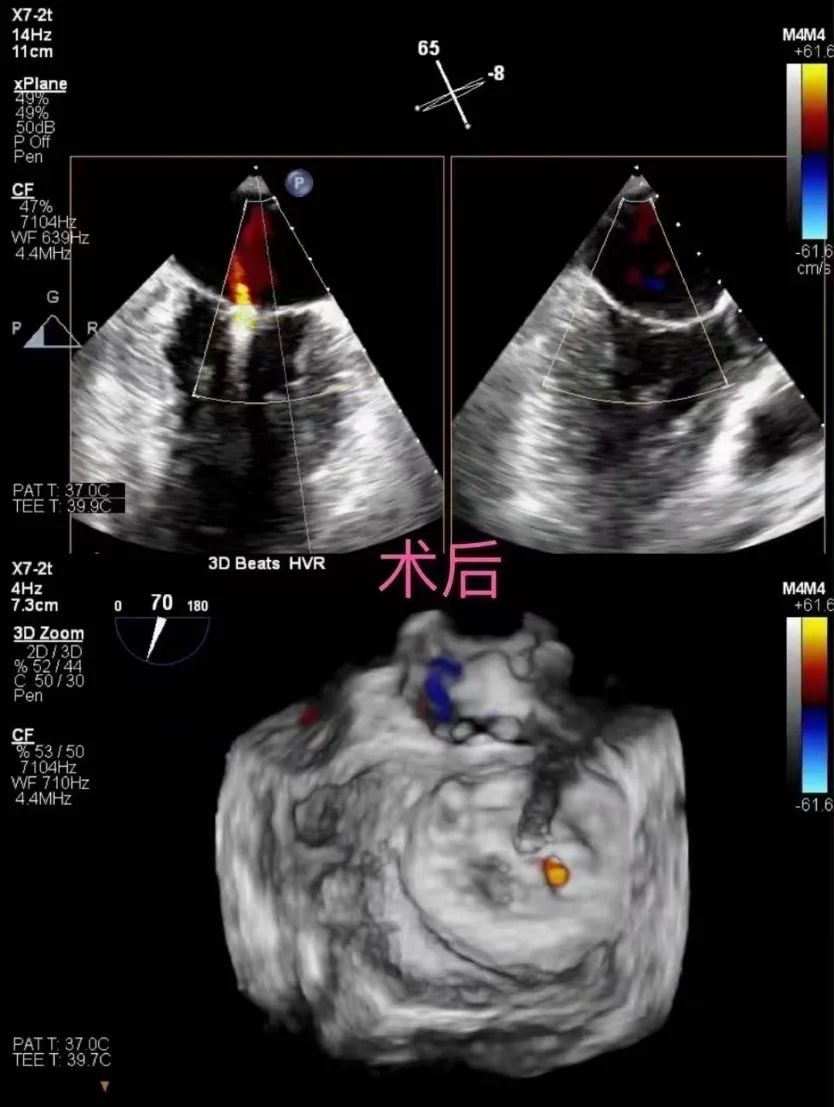

术中陈样新教授团队在超声和X射线引导下经股静脉入路,完成房间隔穿刺,使用能够精确稳定调控的器械旋钮将二尖瓣夹子准确调整到目标区域,反复测试器械运动轨迹和夹子钳夹方向,最终夹子精确的到达了预定位置,夹合了最优的瓣叶长度,获得了最佳的手术效果术后少量反流MR1+。

术后超声图: